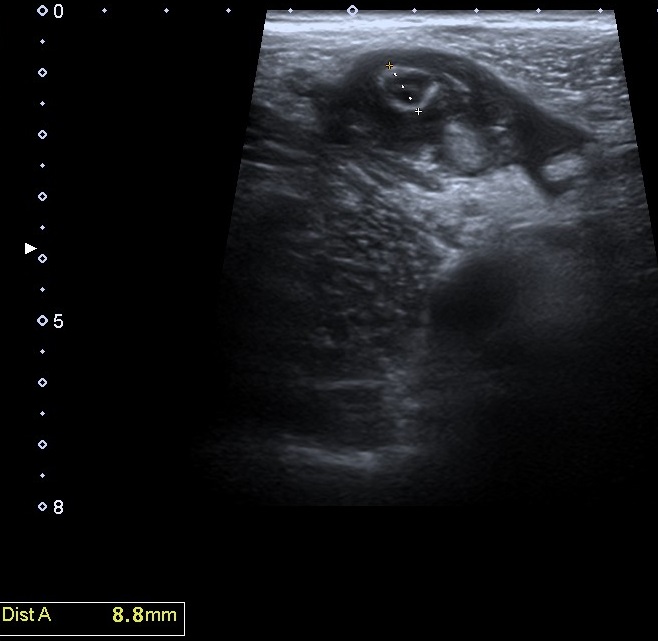

Se realiza una exploración abdominal ecográfica donde se observa hígado de ecogenicidad normal sin lesiones ocupantes de espacio. Vesícula biliar normal, vía biliar no dilatada. Ambos riñones de tamaño y aspecto normales. Páncreas, bazo y aorta normales. En fosa ilíaca derecha se observa apéndice cecal engrosado (imagen 1) con llamativa hiperecogenicidad de la grasa abdominal en relación con cambios inflamatorios (imagen 2). Colección abdominal en relación con cambios inflamatorios 3 x 3 x 5,3 cm (imagen 3).

La ecografía clínica se ha convertido en una herramienta útil para el diagnóstico temprano de apendicitis aguda. Gracias a su accesibilidad, permite realizar una evaluación rápida, ayudando a identificar signos como el engrosamiento del apéndice o la acumulación de líquido periapendicular.